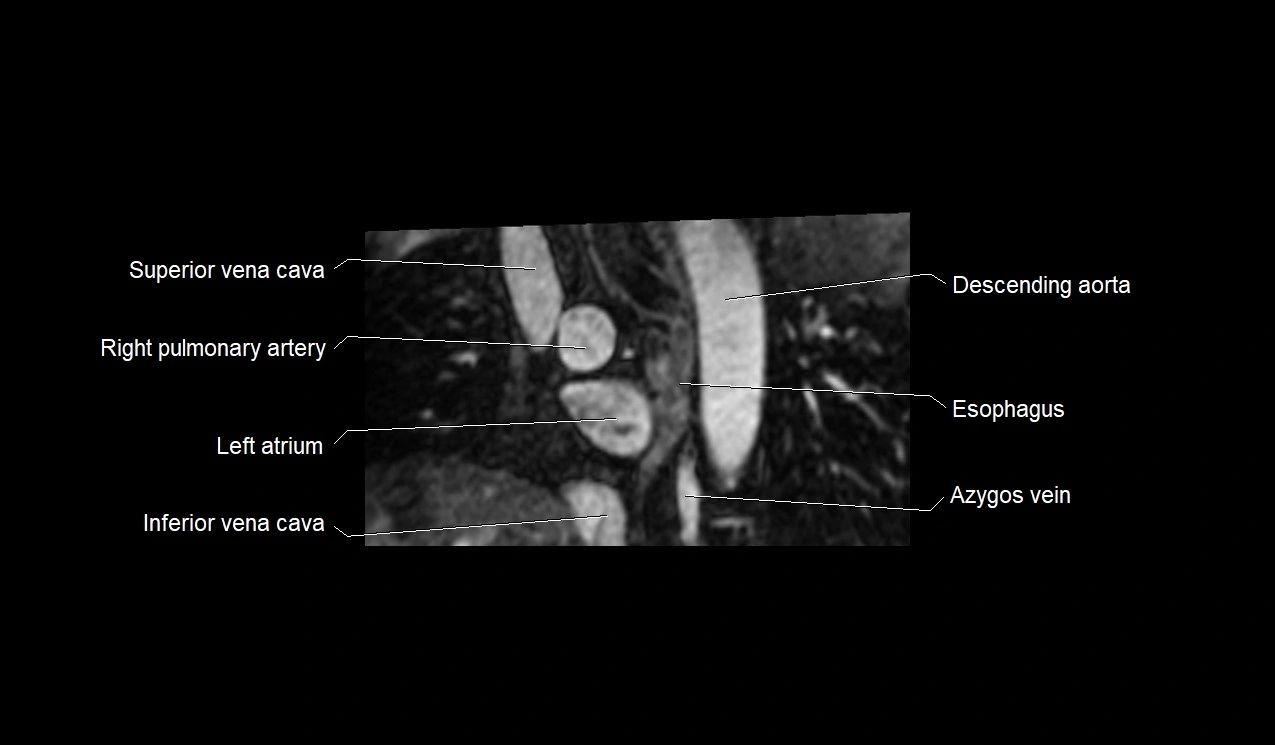

- Superior vena cava

- Right pulmonary artery

- Left atrium

- Inferior vena cava

- Azygos vein